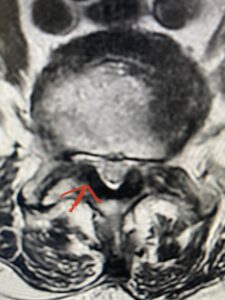

This 73 year-old female had a long history of low back pain and left thigh pain and heaviness of her legs when she ambulated or did activities. She failed all means of conservative treatment including epidurals and PT. On exam she had mild weakness of her left quad but otherwise was intact. Lumbar MRI (Fig 1) revealed significant L4-5 lumbar stenosis and a grade 1-2 spondylolisthesis. Her main pathology was severe, thickened “knobs” of ligamentum forming at the posterior margin of the superior facet processes of L5 and lamina (Fig 2). The patient underwent a decompressive laminectomy of L4 as well as removal of the inferior processes of L5 to widely decompress bilaterally the L4 and L5 nerve roots. Intraoperatively, the descending L5 nerve roots were compressed severely by this severe thickened ligamentum in the subarticular recess. Because of the significant spondylolisthesis we augmented her decompression with fusion. She underwent an L4-5 posterolateral fusion with segmental instrumentation (Fig 3)). Postoperatively she had an uneventful course with relief of her leg pain.

Fig 2 Axial T2-weighted lumbar MRI demonstrating severe lumbar stenosis at L4-5 secondary to thickened ligamentum flavum “knobs” (red arrow) contributing to central and lateral recess stenosis.